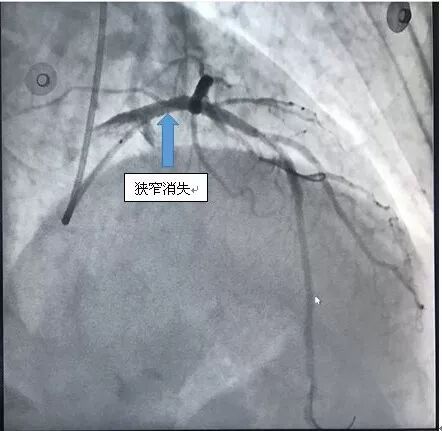

下午4点手术开始,造影显示李爹爹左主干严重狭窄 90%以上,命悬一线。在向病人家属交代病情后,王祥教授带领黄仲略主任和苏华俊主任迅速为患者植入支架,打通血管。血管打通仅花了20分钟。